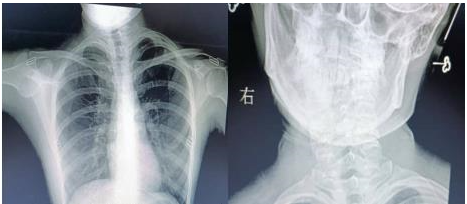

通訊員楊航報(bào)道:18歲的小唐(化名)是個(gè)笑容明媚的在校大學(xué)生,平時(shí)無(wú)論是坐著,站著,走路,脖子就不由自主的偏斜,這種情況讓小唐很困擾。多年來(lái),小唐父母帶她去多家醫(yī)院保守治療,效果還是不理想,經(jīng)過(guò)多方打聽,慕名來(lái)到衡陽(yáng)市中心醫(yī)院骨科一區(qū)求醫(yī)。錢軍副主任接診后詳細(xì)詢問(wèn)病情,結(jié)合相關(guān)輔助檢查,診斷小唐(化名)是“先天性肌性斜頸”。

近日,在蘇光輝主任帶領(lǐng)下,制定完美的手術(shù)方案,與麻醉科及手術(shù)室的共同配合下,順利進(jìn)行了左側(cè)胸鎖乳突肌攣縮胸骨頭+鎖骨頭切斷+胸鎖乳突肌黏連松解+切口美容縫合手術(shù)。術(shù)后經(jīng)過(guò)精心護(hù)理,患者恢復(fù)良好,患者及家屬對(duì)手術(shù)效果非常滿意,現(xiàn)已佩戴支具出院。

錢軍副主任介紹,“先天性肌性斜頸”最常見的原因是患兒出生前胎位不正,頭頸部扭曲,致頸肌肉供血發(fā)生障礙,肌肉變形、逐漸攣縮,引起頸部?jī)蓚?cè)肌肉平衡失調(diào),使頭部偏向變攣縮的一側(cè),形成頭頸側(cè)斜。